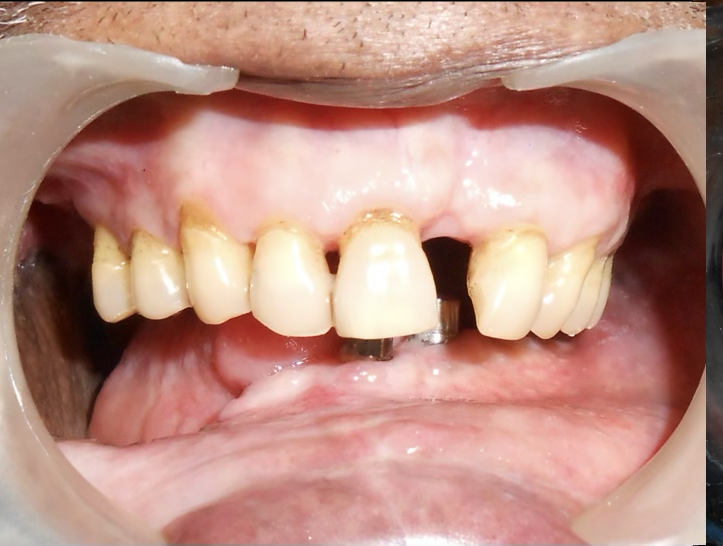

Initial condition

Missing right jaw due to oral cancer surgery, difficulty in chewing, swallowing and speech with mandible deviation

A 72-year-old male oral cancer survivor visited our dental center after surgical removal of the right side of his mandible. Patient had multiple missing and attrited teeth with significant functional impairment. Treatment involved implant-supported lower teeth with PFM crowns and precision-attached removable denture for hemimandibulectomy rehabilitation.

Comprehensive evaluation of oral cancer survivor post-hemimandibulectomy. Patient presented with missing teeth 16, 17, 25, 26, 31-37 and excised right mandible. Complete assessment of remaining bone and soft tissue.